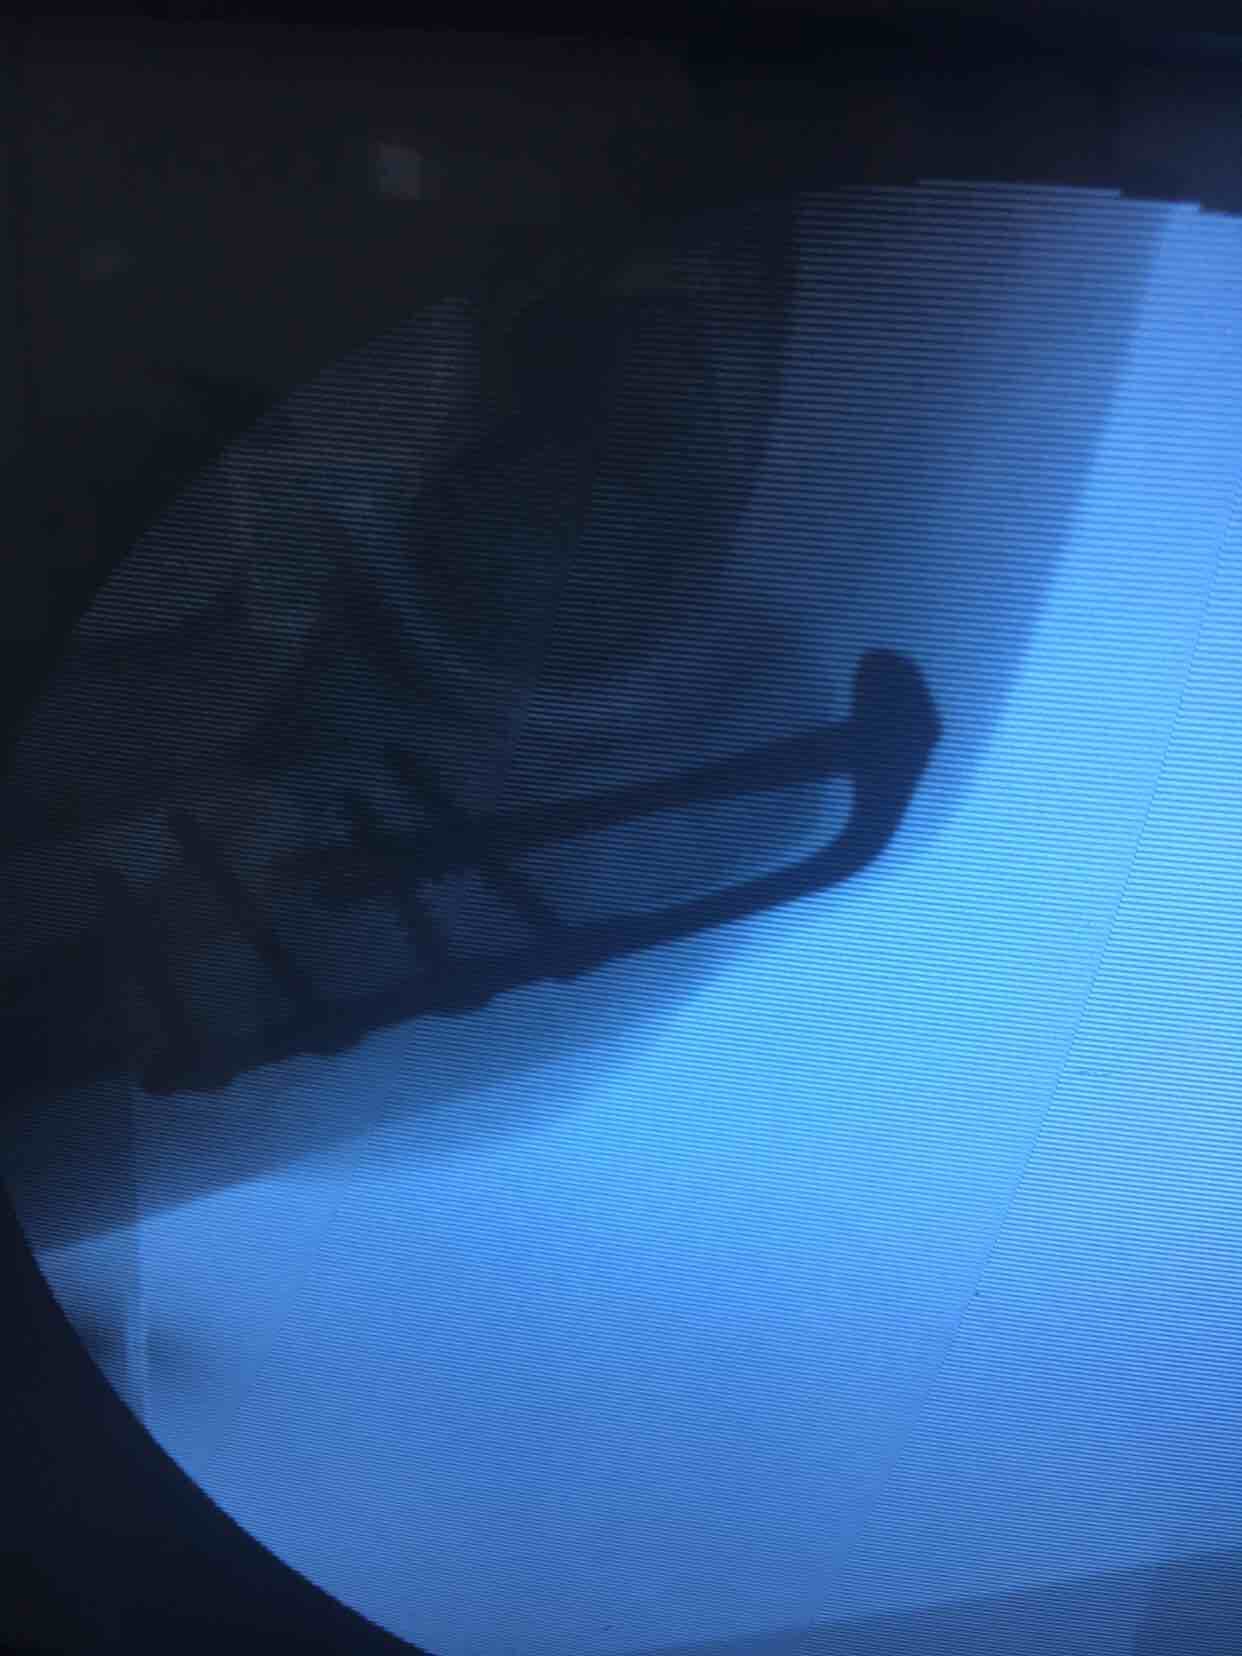

尺骨鹰嘴骨折(切复内固定术)

诊断右尺骨鹰嘴骨折在臂丛麻醉下行切复内固定术,术后抗炎,消肿等处理。